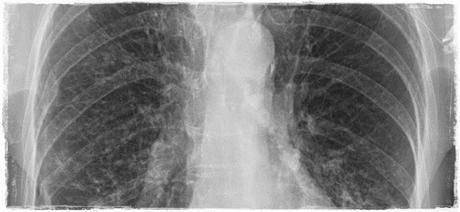

A nivel respiratorio pueden ocurrir bronquitis de repetición, tos recurrente inexplicable por otras causas, infecciones respiratorias recurrentes, bronquiolitis de evolución tórpida... dando lugar a un daño pulmonar progresivo.